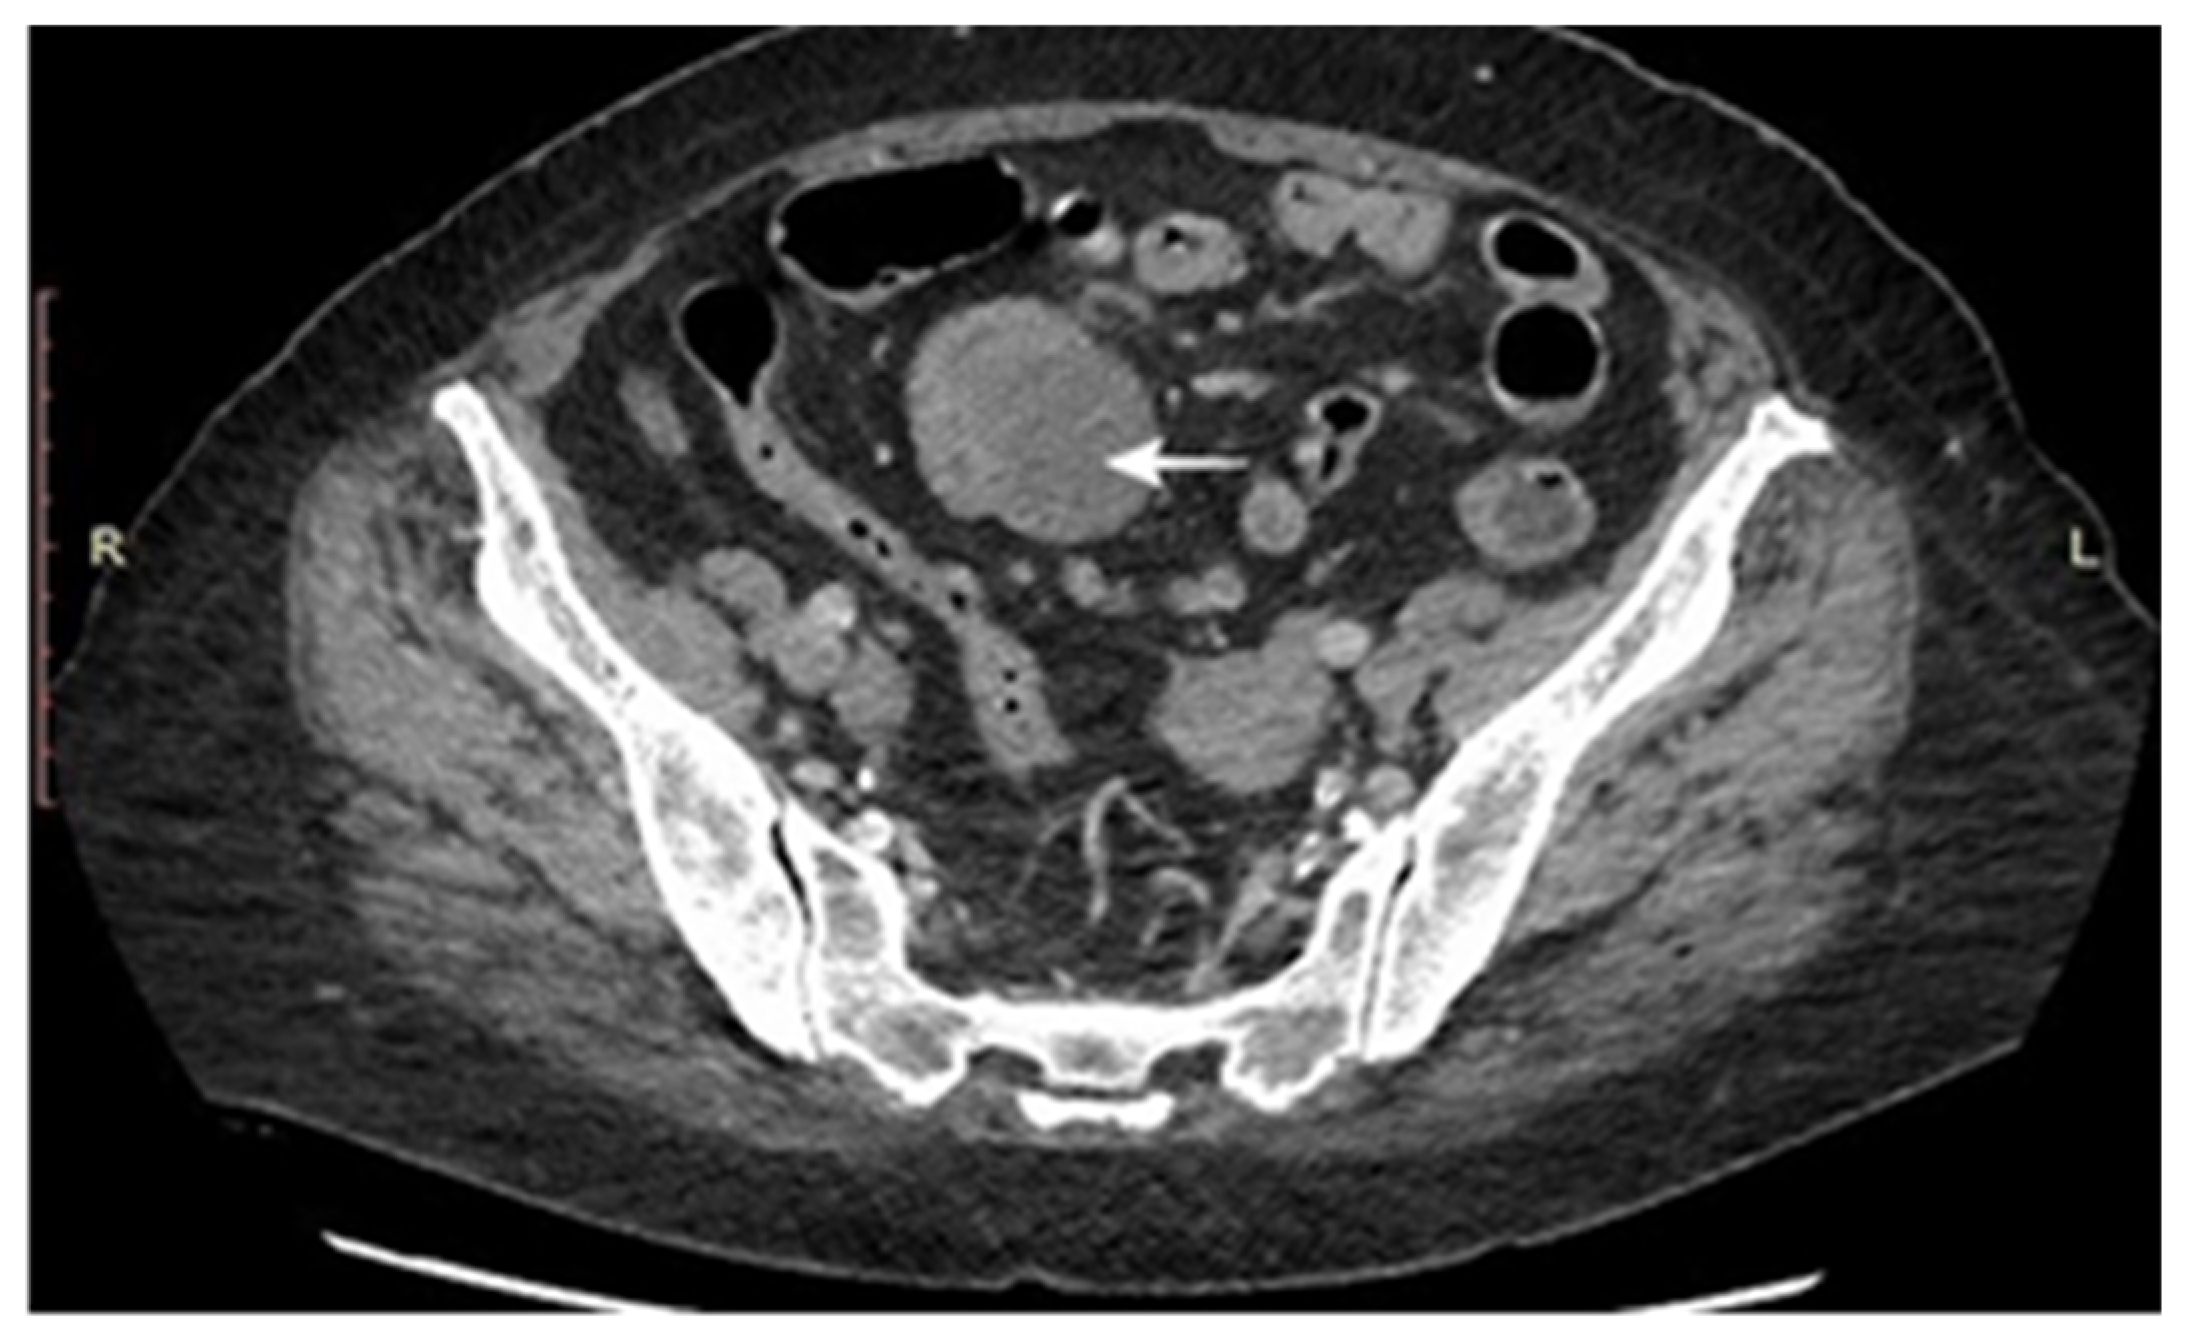

3.1. Main Characteristics of Patients

| CT scan number | 48 (60) |

| Tumor (%) | 39 (81.3) |

| Lymph nodes (% from malignant tumors) | 12 (33.3) |

| Metastasis (% from malignant tumors) | 22 (37.9) |

| Transabdominal ultrasound [No (%)] | 21 (26.3) |

| Tumor | 4 (19) |